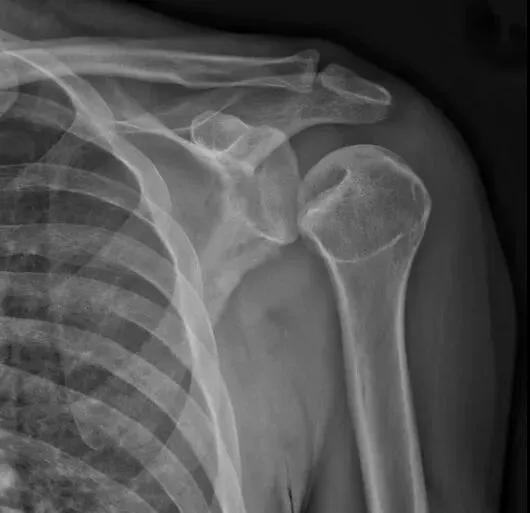

了解完肩关节X线解剖结构后,我们再来看正常的肩关节,肱骨头与关节盂是有部分重叠的,称为半月重叠征,或半月征。

当发生后脱位时,肱骨头与关节盂前缘距离大于等于7毫米,甚至关节盂变为空虚,

表现为关节盂前缘形成类似环的影像,称为环征。